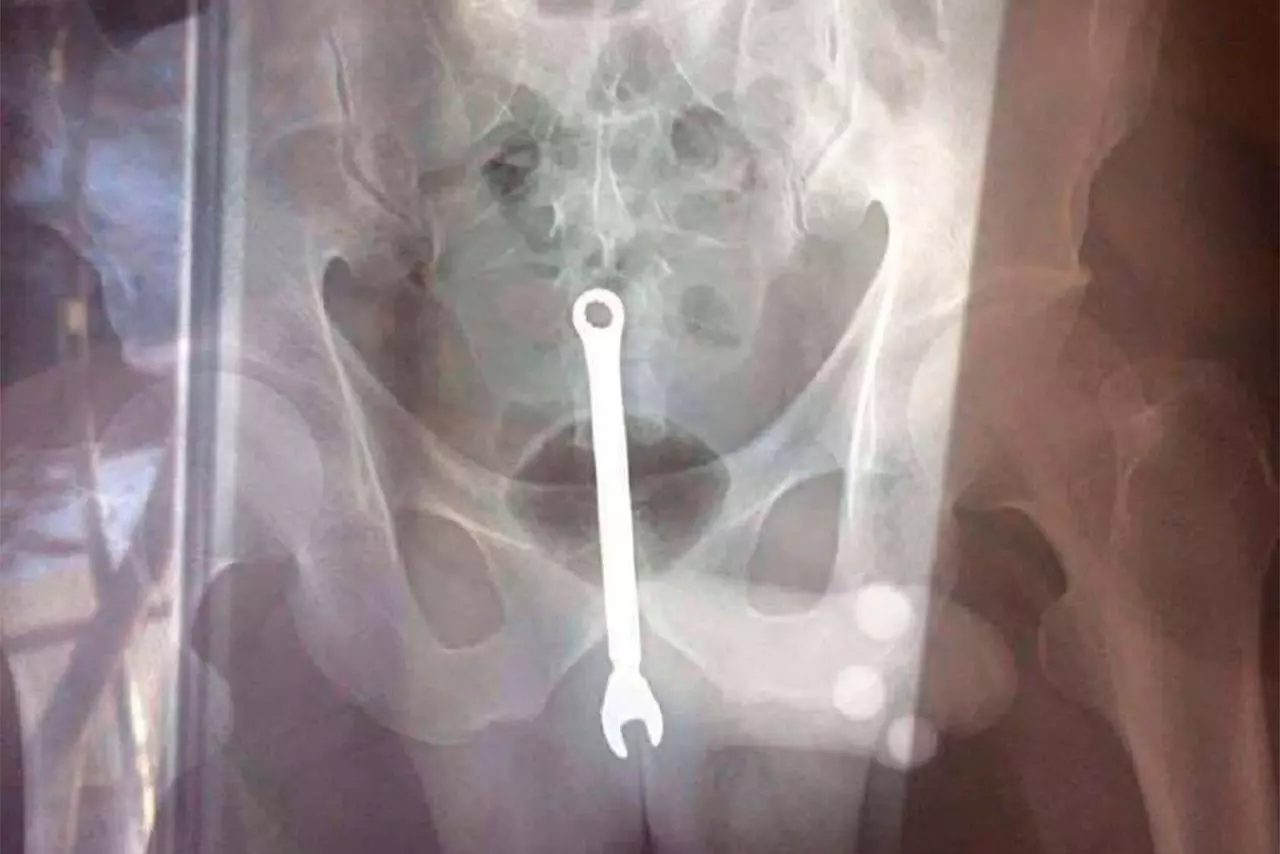

Московский автослесарь дважды за новогодние праздники обратился к врачам из-за гаечного ключа в заднем проходе.

Работник одной из столичных ремонтных мастерских впервые пришел к медикам в конце декабря и сообщил, что в нем находится инструмент.

Мужчина заявил, что упал на гаечный ключ случайно, и врачи извлекли инородное тело.

Во время новогодних праздников пациент снова обратился в приемное отделение и рассказал, что гаечный ключ опять оказался в его заднем проходе.

По словам пострадавшего, он выпивал с коллегами в автосервисе, затем между ними завязалась драка, в результате которой ключ попал в него.

Врачи снова извлекли инструмент, который пациент забрал с собой.